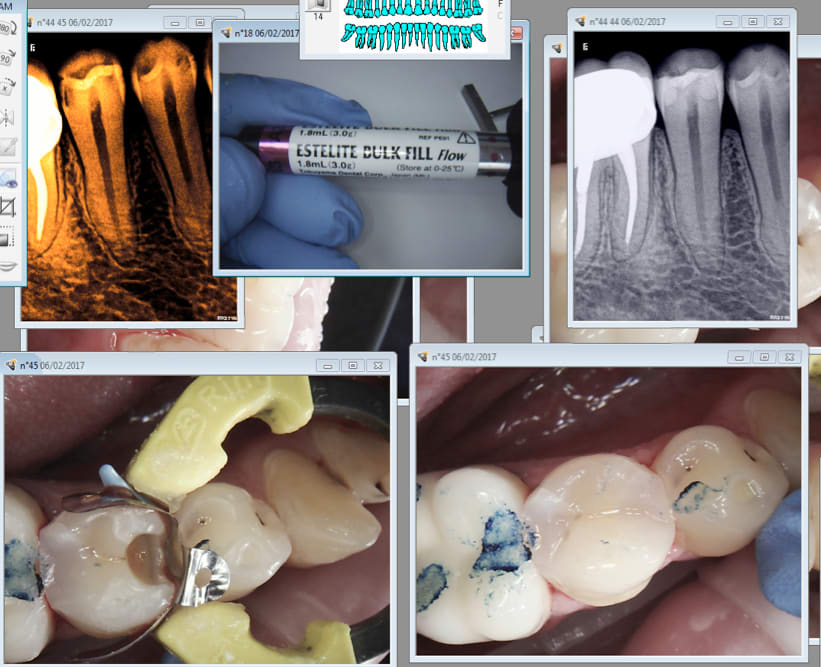

06/02/2017 à 14h55

Estellitte bulk fill. En une couche.

Capture d écran 2017 02 06 14.53 - Eugenol

Re essai bulk fill estelite flow